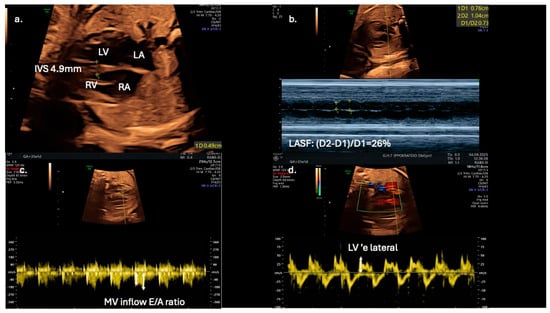

From a clinical perspective, fetal echocardiography may serve as an adjunct tool for predicting neonatal metabolic complications. Fetal IVS hypertrophy demonstrates a strong association with increased risk of neonatal hypoglycemia, hyperbilirubinemia, prolonged admissions to intensive care units, and persistent fetal shunts (e.g., patent ductus arteriosus and patent foramen ovale). However, fetal cardiac dysfunction, as evaluated by Doppler and TDI, does not reliably predict adverse perinatal events such as intrapartum fetal distress or perinatal asphyxia [13]. Speckle-tracking echocardiography is showcased as a more sensitive tool for detecting subtle fetal cardiac dysfunction, and its assessment should be considered for all fetuses of mothers with diabetes, even in the absence of septal hypertrophy, which may appear later as a less sensitive marker (Figure 3).

Echocardiographic indices in a 31-gestational-week fetus of a diabetic mother; (a) interventricular septal thickness (IVS) measured in the four-chamber view; (b) in the same view, left atrial systolic shortening (LASF) is calculated using M-mode echocardiography; (c) use of pulse wave Doppler imaging in mitral inflow to calculate E/A ratio; (d) application of tissue Doppler imaging in the lateral wall of the left ventricle enables further assessment of diastolic function by calculating ‘e wave and E/’e ratio.

Early detection of diastolic dysfunction could also have significant implications for postnatal cardiovascular health [9]. Left atrial shortening fraction could serve as an adjunct novel echocardiographic parameter for evaluating diastolic function in fetuses of diabetic mothers and may improve prenatal cardiac monitoring and management (Figure 3). In addition, Mod-MPI and E/A ratio could be utilized as early biomarkers of distress, as they are possibly more sensitive than conventional tools, such as cardiotocography and umbilical artery Doppler velocimetry. for predicting adverse perinatal outcomes in gestational diabetic pregnancies. The suggested high sensitivity and specificity thresholds (100% and 92%, respectively) for Mod-MPI ≥ 0.52 shown by Bhorat I.E. et al. highlight the need for further validation of its potential clinical utility in risk stratification and surveillance protocols [12].